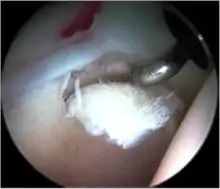

![]() Intraoperative fluoroscopic image during an arthroscopic resection of a cam lesion of the femur. The upper instrument is the arthroscope (viewing device), while the lower is the high-speed burr used for reshaping the bone. |

Standard arthroscopic treatment of symptomatic cam FAI involves debridement (resection) or repair of any labral [10] and chondral injuries [11] in the central compartment of the hip, and subsequent reshaping of the head-neck junction of the upper femur (osteochondroplasty) in the peripheral compartment [12][13] using high-speed motorised burrs that are similar in design to a dentist's drill (see fig. 9).